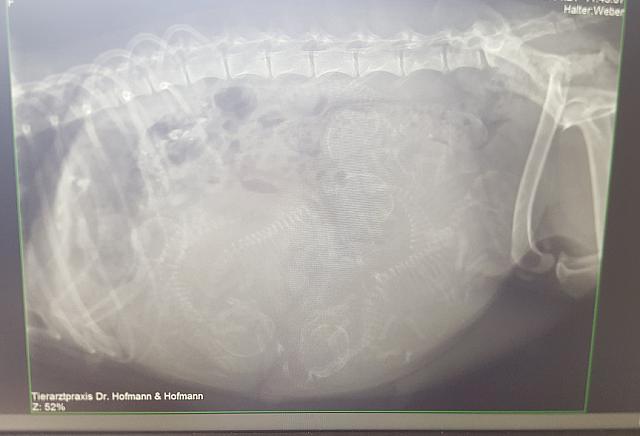

21.04.18 = Am 56. Trächtigkeitstag haben wir bei unserem Tierarzt ein Röntgenbild anfertigen lassen, damit wir uns auf die Anzahl der Hunde-Babys einstellen können.